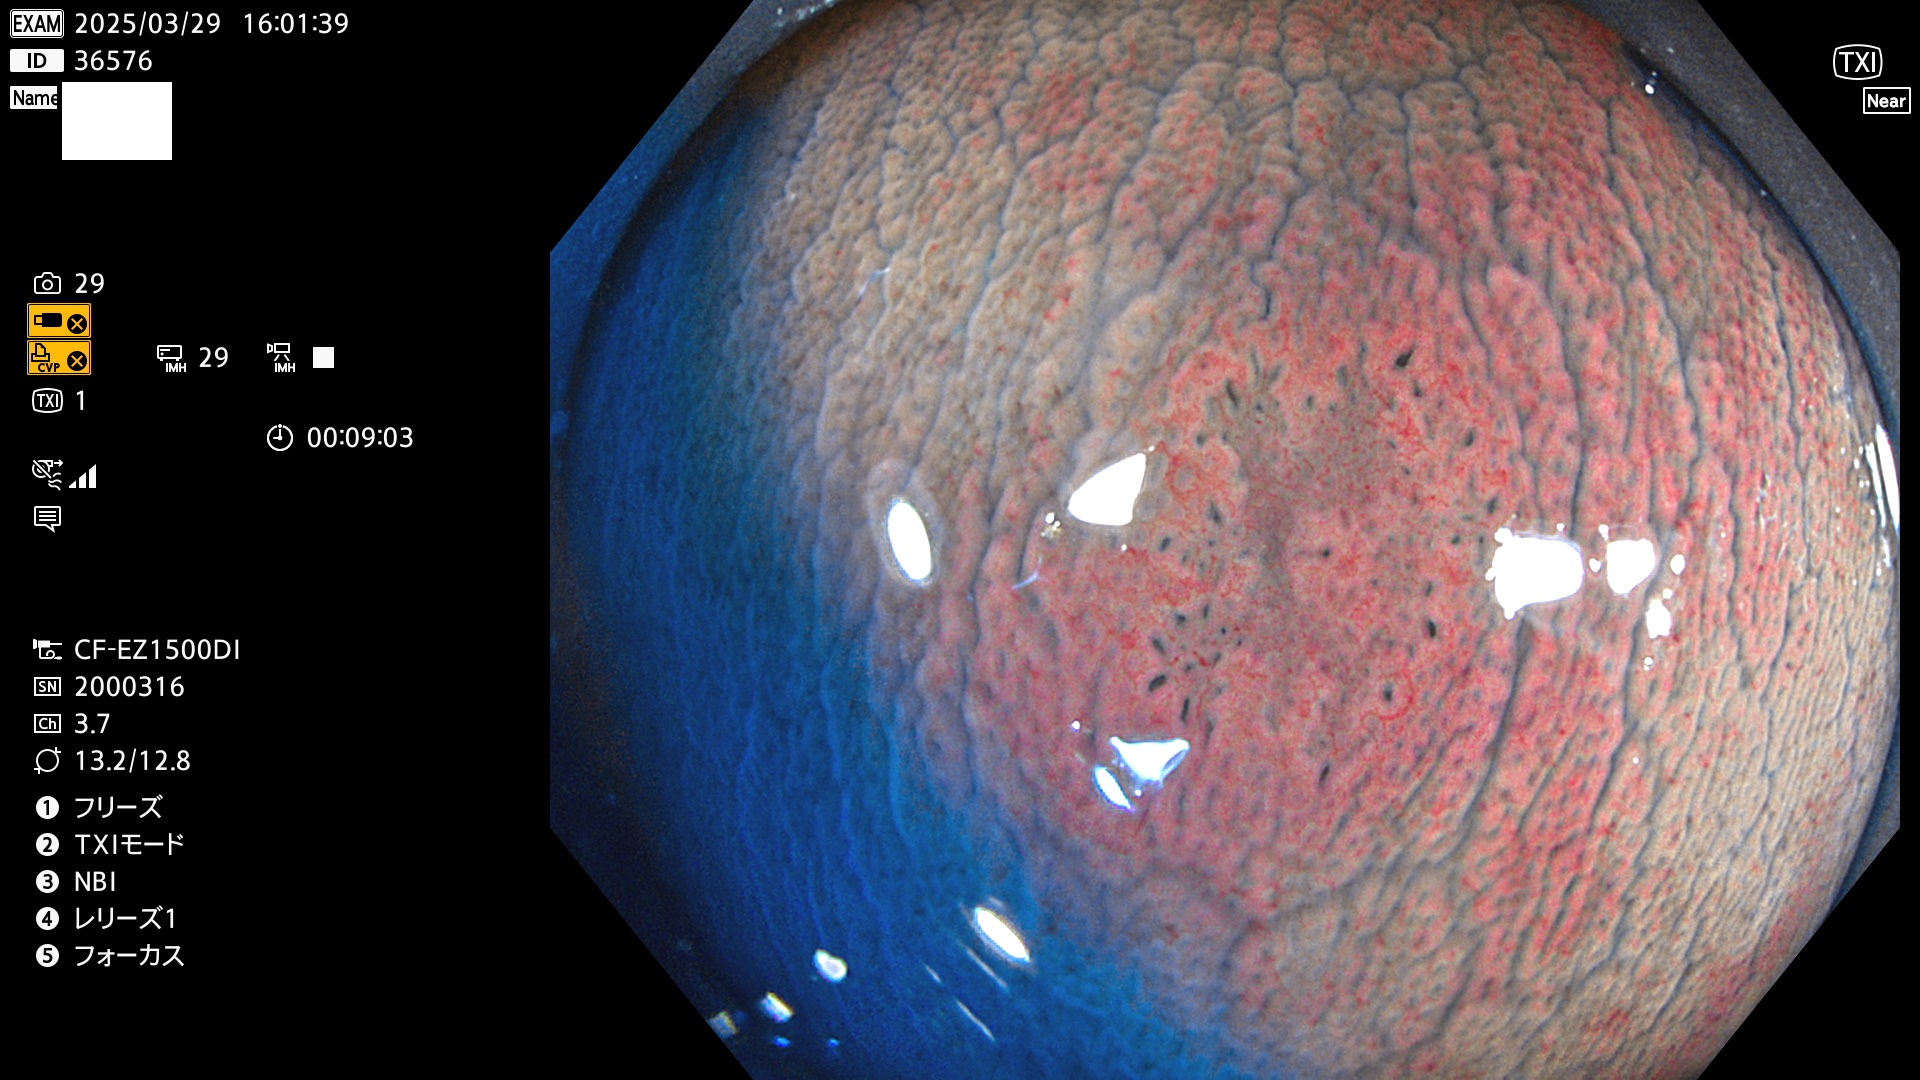

完全に平坦な物をUb、陥凹している物をUcと呼びます。Ubは認識が困難で、Ucはびらん(炎症)と紛らわしいために見落とされやすく、「内視鏡後・大腸癌」の原因になります。

抽出の対象期間 2025年3月27日〜3月30日の4日間(48件の検査)8個 (8/48=16%)